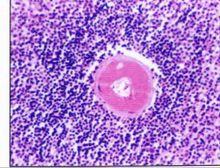

1.淋巴細胞增生性表現:100%的ALPS病例均有脾臟腫大,多於5歲內發現,甚至發生在胎兒期。脾腫大的程度不一。74%的病兒因脾功能亢進或脾破裂而行脾切除術。67%的患兒有輕到中度肝大,偶爾發現肝功能異常。約97%的患兒全身性淺表淋巴結腫大,影像學可發現縱隔淋巴結腫大。

自身免疫性淋巴細胞增生綜合徵T淋巴細胞CD3+細胞數量增多,超過CD4T細胞和CD8+ T細胞的總和提示存在CIM- CD8- T細胞亞群且其TCR為α/β鏈(正常人僅偶爾出現,常低於1%,而ALPS患兒常高於5%~20%,甚至達68%)。這些CD4- CD8- T細胞是未進入凋亡的衰老細胞。